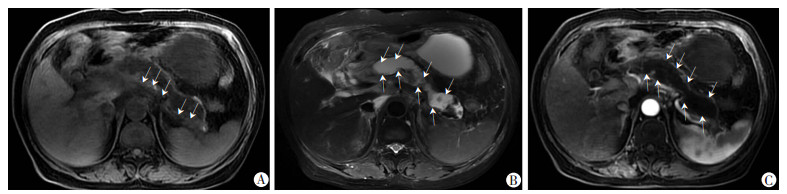

将IVIM-DWI与DTI原始图像数据传输至GE 4.4 Workstation。应用FuncTool 2软件包中的MADC软件和DTI软件对IVIM-DWI、DTI的原始数据进行后处理,以阈值法除去周围骨、气体、脂肪等组织的影像,获得MADC、DTI图,并测量其胰腺头、体、尾处感兴趣区(Region Of Interest,ROI)下单指数模型(Standard ADC)和双指数模型的参数值Slow ADC、Fast ADC、Ff ADC(图 1),以及DTI参数值ADC、FA,取胰腺头、体、尾的平均值为以上参数值(图 2)。ROI的选取:DWI图像上呈高信号区域(以T2WI图像作为依据)选取3个相同面积ROI测量各参数值,并连续测量上下三层面计算其平均值,尽量避开主副胰管、血管和明暗伪影带等。

| A:DWI图;B:Slow ADC图;C:Standard ADC图;D:Fast ADC;E:Ff ADC在胰体放置3个大小相等的ROI测量各参数 图 1 AP患者的IVIM-DWI各参数测量图 |

2 结果 2.1 AP严重程度MRI评价85例AP中,糖尿病、高血压或高脂血症引起的28例,胆源性21例,饮食、饮酒19例,胆囊切除术后11例,其他6例。依据MRI表现,85例AP中间质水肿型66例(77.6 %),出血坏死型19例(22.4%),见图 3、4。依据MRSI分型:轻度32例(37.6 %),中度40例(47.05 %),重度13例(15.3%)。

|

箭头示:胰腺体尾部肿胀,边缘模糊,边缘有少量渗出 A:T1WI;B:T2WI;C:T1增强胰腺实质均匀强化,未见坏死区域,MRSI评分2分,严重程度为轻度 图 3 间质水肿型AP患者(50岁女性)MRI表现 |